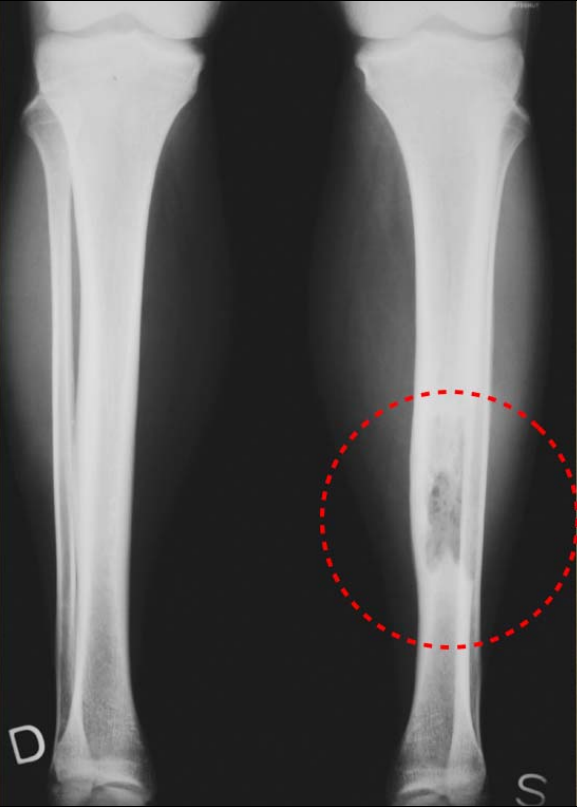

Figure1